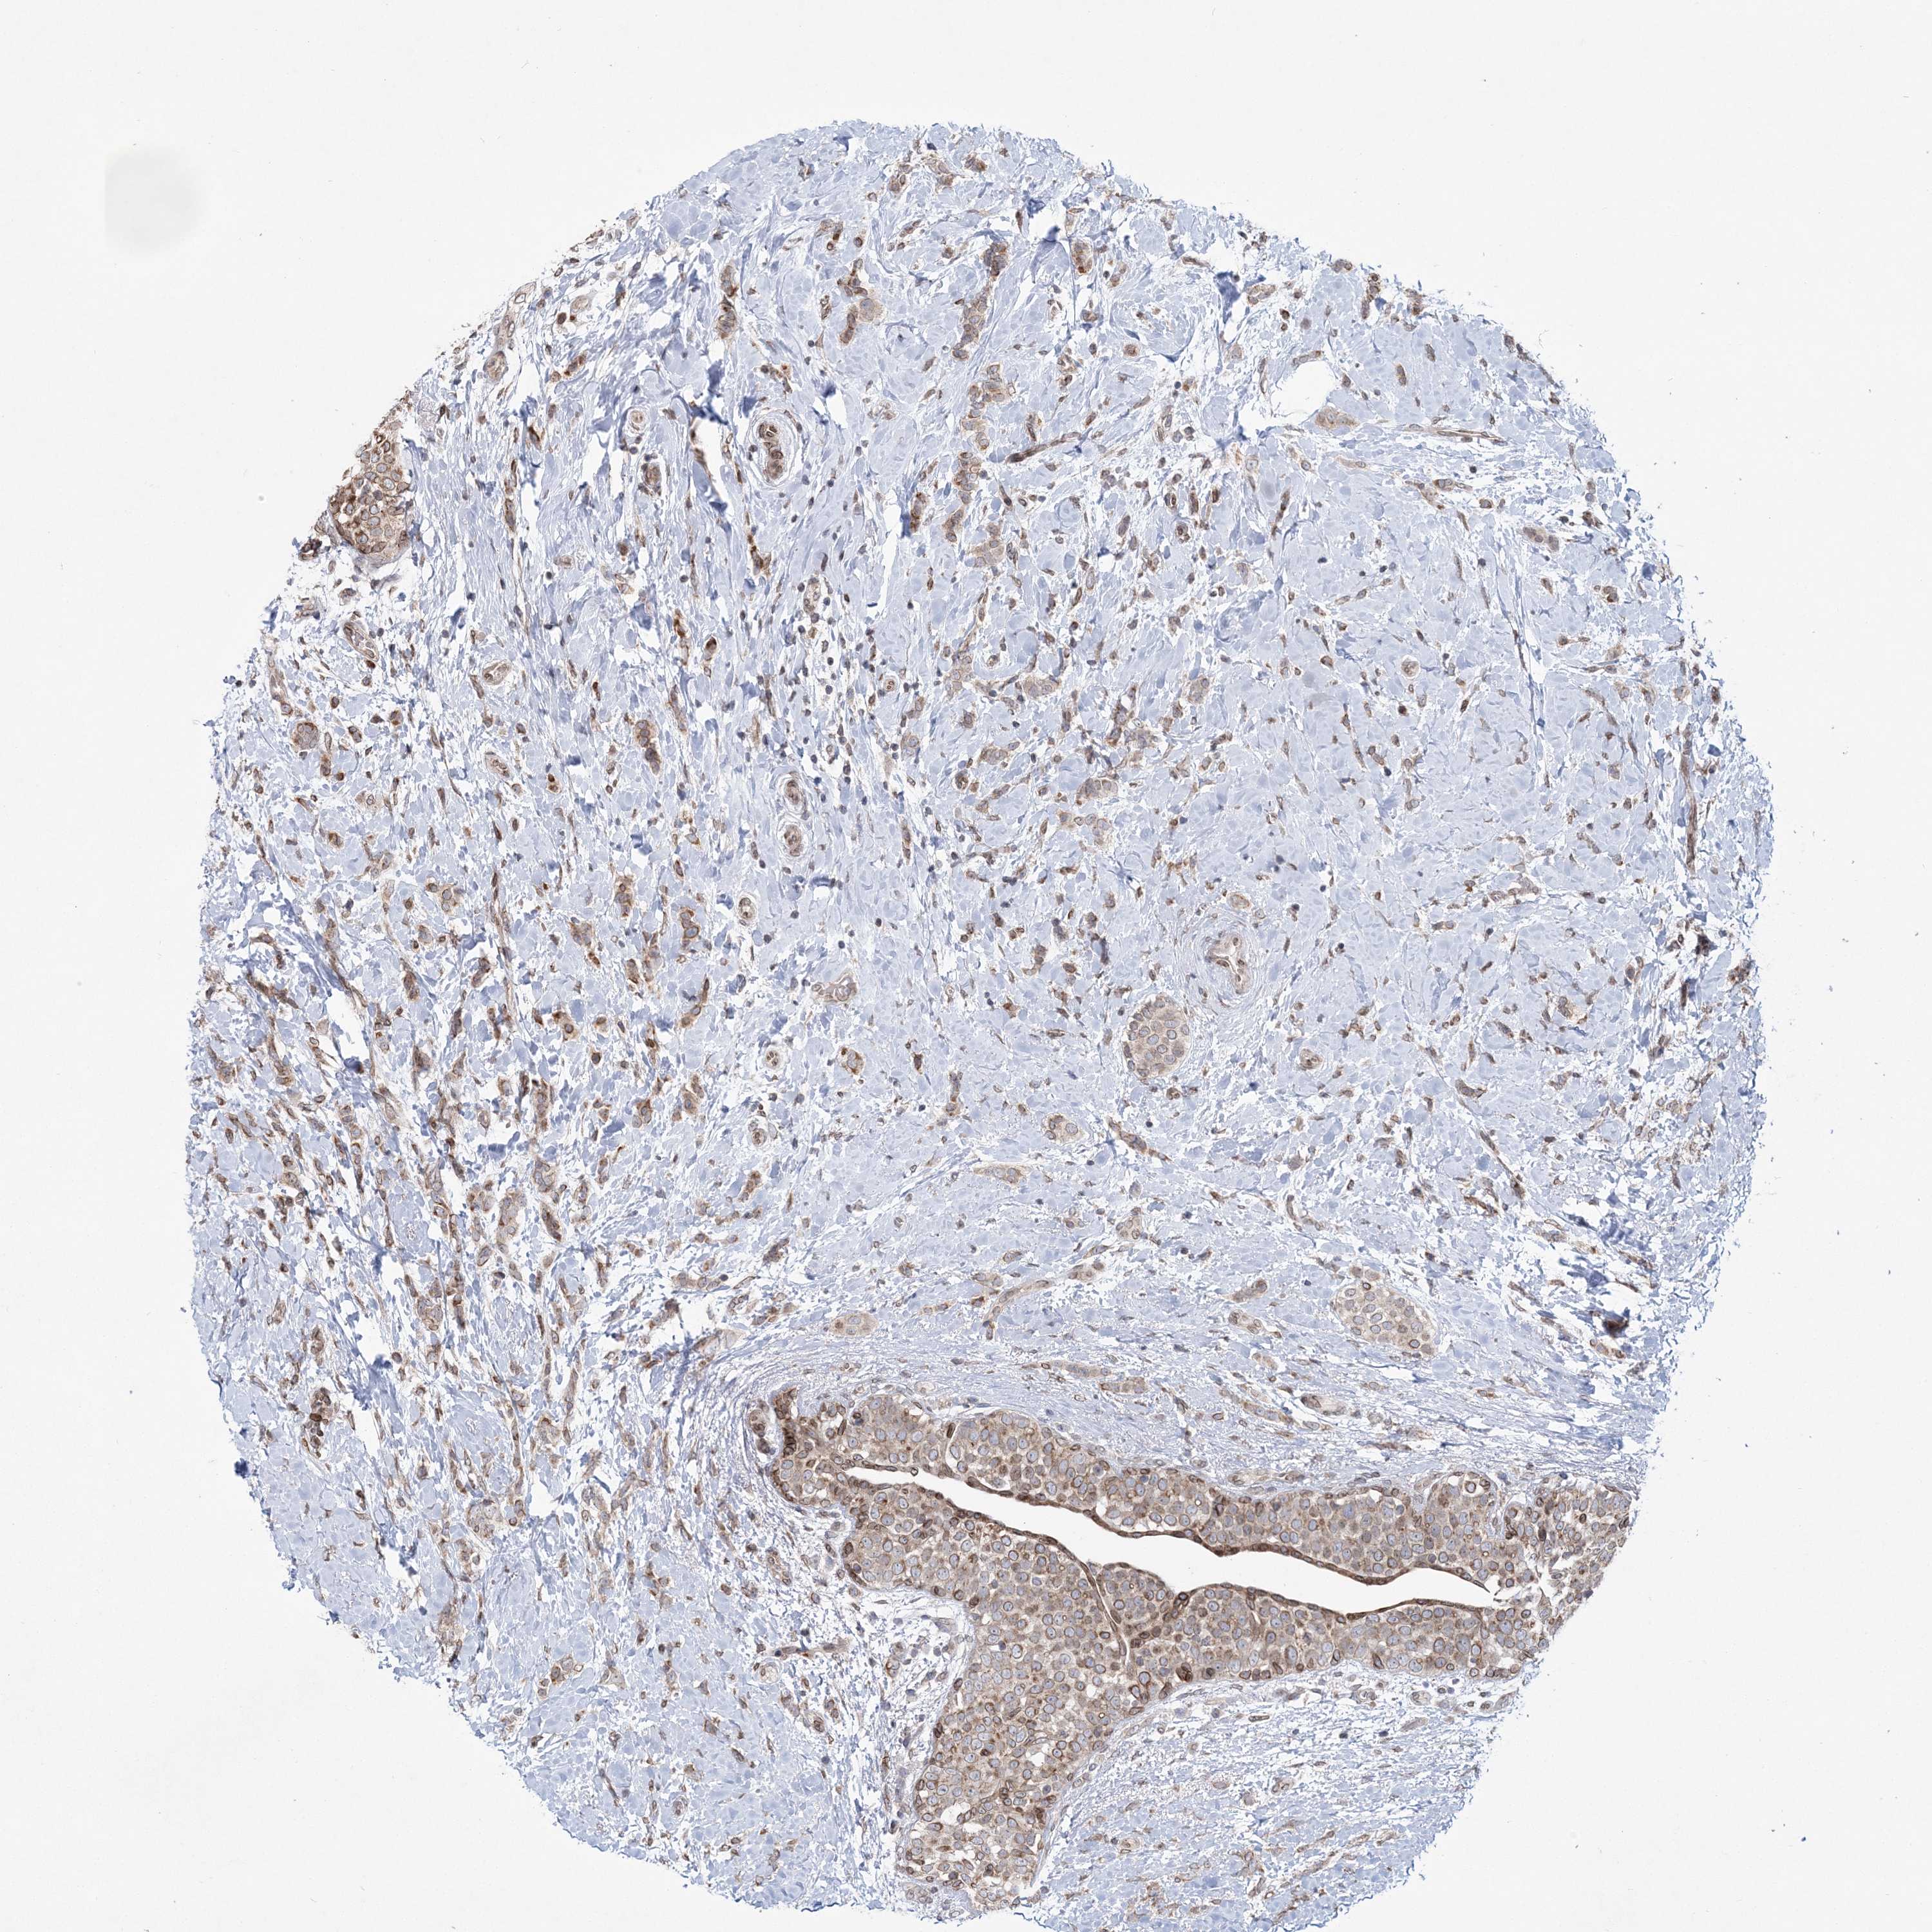

CANCER BREAST CANCER Show tissue menu

BRCA TCGA BRCA VALIDATION PROTEIN EXPRESSION

ANTIBODIES

AND

VALIDATION